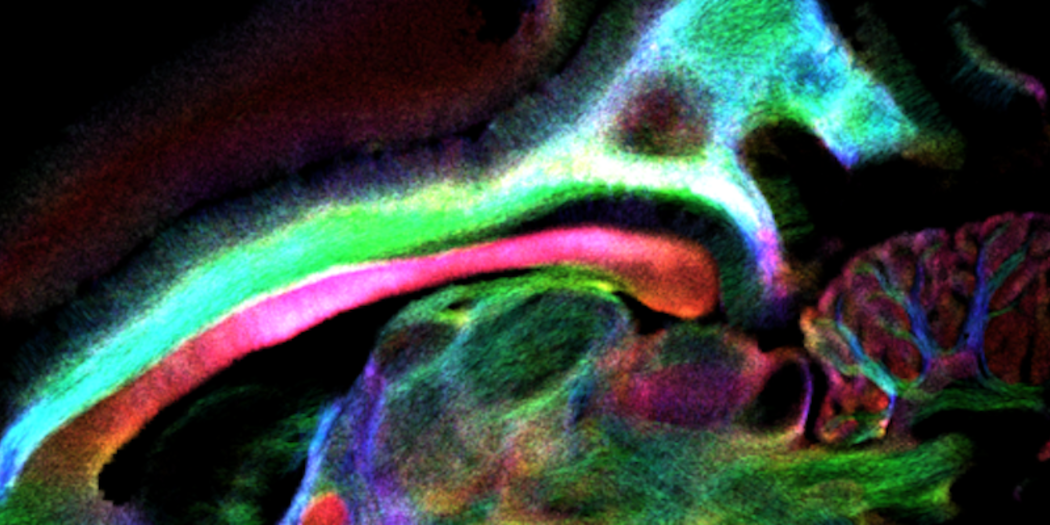

In vivo mouse brain with 29 µm resolution, measured at 15.2 T with MRI CryoProbe. Acquisition details: RARE, resolution: (29 × 29 × 200) µm³, TR: 3.5 s, TE: 25 ms, echoes: 6, slices: 7

In preclinical MRI, cryogenically-cooled MRI CryoProbes [2], provide an additional sensitivity boost [3] and have found widespread use. Combined with UHF MRI, the additional gain is significant and enables highest quality images in reasonable measurement times [4]. Thus, for example, ultra high resolution in vivo mouse brain data can be easily acquired on a preclinical 15.2 Tesla equipped with a MRI CryoProbe.